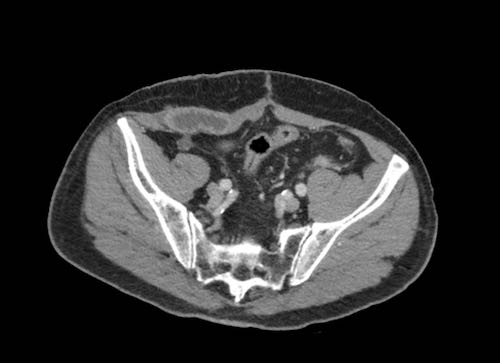

Ca lâm sàng 2

Cuộn qua các lát cắt.

Bạn có thể phát hiện tất cả các tổn thương cấy ghép phúc mạc không?

.jpeg)